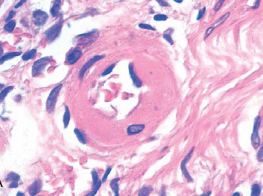

what pathology is this?

name three visible characteristics:

hyaline arteriolosclerosis

1. narrowed lumen

2. izedincreased protein deposition (hyaline)

3. thickened arteriolarl wall